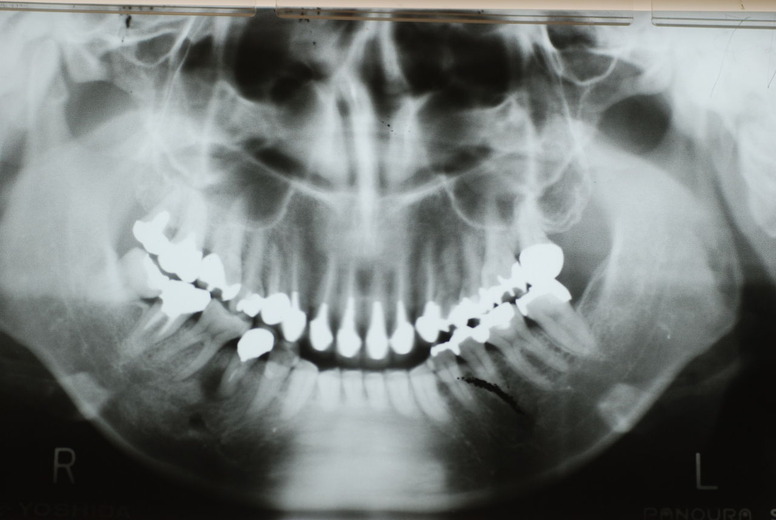

歯周病になっていましたが、少し色が黄色くなっているだけで比較的綺麗な歯の状態です。

平成9年来院神経を取り、同時に歯周病の話をしてそのまま来なくなっていたかたですが、たまたま一部欠けてきました。それで来院。

平成9年![40af2ca7-s[1]](https://livedoor.blogimg.jp/netdental/imgs/0/d/0d02b3dc.jpg)

平成24年一部欠けて来院